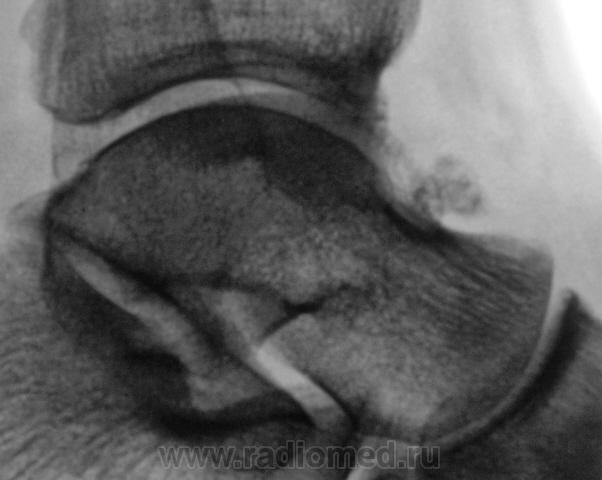

Трах... и вырос "грибок" на таранной...

Грибок этот не "трахогенной" природы. У меня вообще сомнения, что это вырост кости.

Понятно конечно, что "грибок" случайная находка. Но травма была...

Лодыжка срастется, никуда не денется. А вот оссифицирующий апоневрозит и данный то-ли экзостоз, то-ли оссификат капсулы будут периодически доставать и пациента, и врача-куратора.

Больше склоняюсь к хондромному телу, хоть в данном месте не встречал

Грибок этот не "трахогенной" природы. У меня вообще сомнения, что это вырост кости.  +1 !     Больше похоже на обызвествление сосудов . А хондроматоз - не подходит по локализации , хотя сама тень похожа внешне .